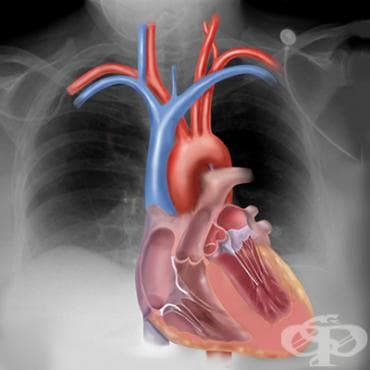

Сърдечно-съдовите заболявания остават водеща причина за смъртност в световен мащаб, но голяма част от тях могат да бъдат предотвратени чрез здравословен начин на живот, навременни прегледи и подходящо лечение. Лекари и специалисти призовават хората да обръщат внимание на симптоми като задух, умора, болка или тежест в гърдите и да не отлагат профилактичните прегледи.

Именно един такъв профилактичен преглед променя живота на Владимир Симеонов от Годеч. При рутинна проверка лекарите откриват разширена аорта и проблем с аортната клапа - състояние, което при забавяне може да бъде животозастрашаващо.

Преди две години 65-годишният международен шофьор посещава личния си лекар за преглед. Джипито го насочило към кардиолог, където ехограф показва разширение на аортата, а допълнителните изследвания потвърждават и пропускане на аортната клапа. Медиците предупреждават, че при рязко физическо натоварване съществува риск от спукване на аортата - животозастрашаващо състояние.

"Казаха ми, че трябва да се оперирам навреме, защото после става много по-трудно. Съгласих се и в Окръжна болница ми смениха клапата и част от аортата", разказва Владимир.